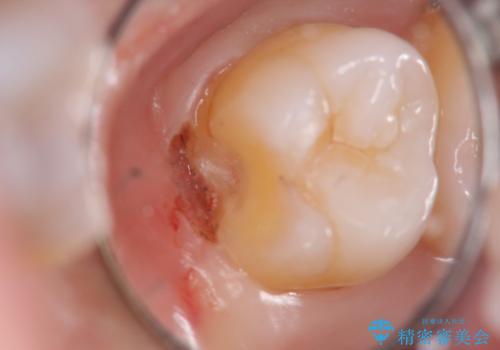

- 検査の結果、左上の一番奥の歯のさらに奥の面の深い位置に虫歯が潜んでいることを確認しました。

外から見えない位置であるため、セラミックよりも精度を上げることができるゴールド(PGAインレー)で修復していきます。

昔親知らずが埋まっていた場所にできてしまった虫歯であるためかなり深い位置に潜り込むような虫歯でした。

このような虫歯でも丁寧に処置することで問題なく適合の良いインレーを入れることができます。